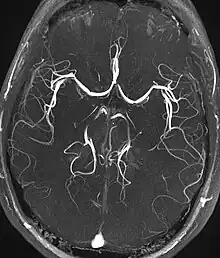

A angiografia por ressonância magnética (MRA) gera imagens das artérias para avaliá-las para estenose (estreitamento anormal) ou aneurismas (dilatação da parede vascular, em risco de ruptura). O MRA é frequentemente usado para avaliar as artérias do pescoço e do cérebro, a aorta torácica e abdominal, as artérias renais e as pernas (chamado de "escorrer"). Uma variedade de técnicas podem ser usadas para gerar as imagens, como a administração de um agente de contraste paramagnético (gadolínio) ou usando uma técnica conhecida como "aprimoramento relacionado ao fluxo" (por exemplo, sequências de tempo de voo 2D e 3D), onde a maior parte do sinal em uma imagem é devido ao sangue que recentemente se mudou para esse plano. As técnicas que envolvem acumulação de fase (conhecida como angiografia por contraste de fase) também podem ser usadas para gerar mapas de velocidade de fluxo com facilidade e precisão. A venografia por ressonância magnética (MRV) é um procedimento similar que é usado para imagens de veias. Neste método, o tecido agora está excitado inferiormente, enquanto o sinal é recolhido no plano imediatamente superior ao plano de excitação - criando assim o sangue venoso que recentemente se moveu do plano excitado.[49]

| Angiografia e venografia por Ressonância Magnética (MRA) | Voo de tempo | TOF | O sangue que entra na área de imagem ainda não está saturado magneticamente, dando um sinal muito mais alto ao usar tempo de eco curto e compensação de fluxo. | Detecção de aneurisma, estenose ou dissecção.[86] | ![]() |